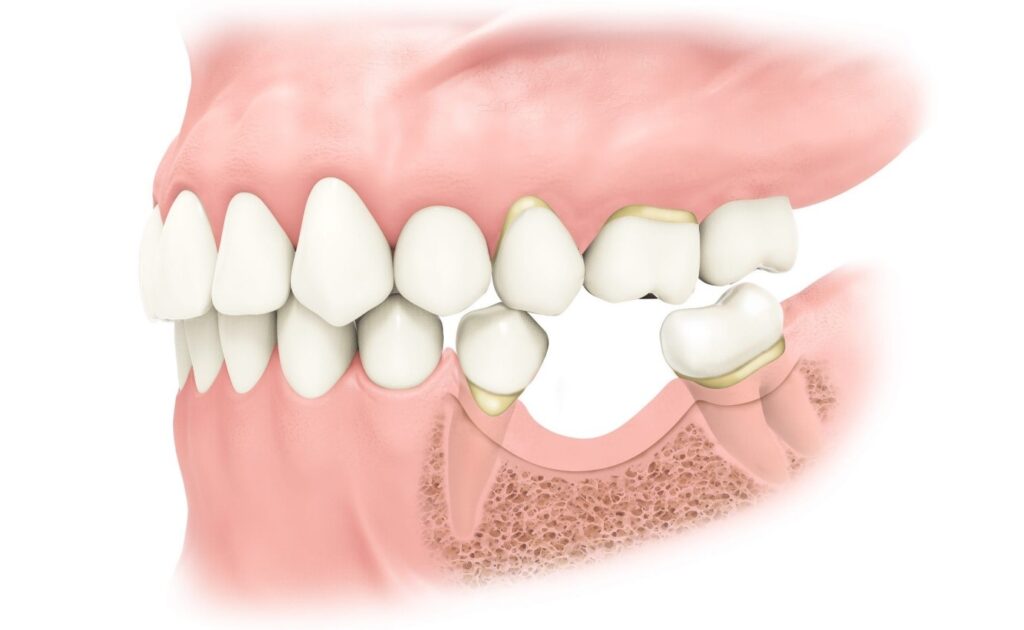

وقتی دندانی کشیده می شود، به مرور زمان استخوان ناحیه دچار تحلیل می شود.

اگر این تحلیل شدید باشد، دیگر امکان قرار دادن ایمپلنت با طول و قطر مناسب وجود ندارد و احتمال شکست درمان بالا می رود. در چنین شرایطی، متخصص جراحی فک و صورت یا ایمپلنتولوژیست با انجام پیوند استخوان پیش از کاشت ایمپلنت تلاش می کند:

- حجم و ارتفاع استخوان فک را بازسازی کند

- تراکم استخوان را به سطح قابل قبول برساند

- موقعیت ایمپلنت را در ناحیه ایده آل (از نظر زیبایی و عملکرد) فراهم کند

- ریسک لقی ایمپلنت، تحلیل بیشتر و عوارض بعدی را کاهش دهد

این پیوند می تواند در ناحیه فک بالا (مثلاً در قالب لیفت سینوس) یا در فک پایین انجام شود و بر اساس نوع ماده مورد استفاده به سه دسته اصلی تقسیم می شود: اتوگرافت، آلوگرافت و زنوگرافت.